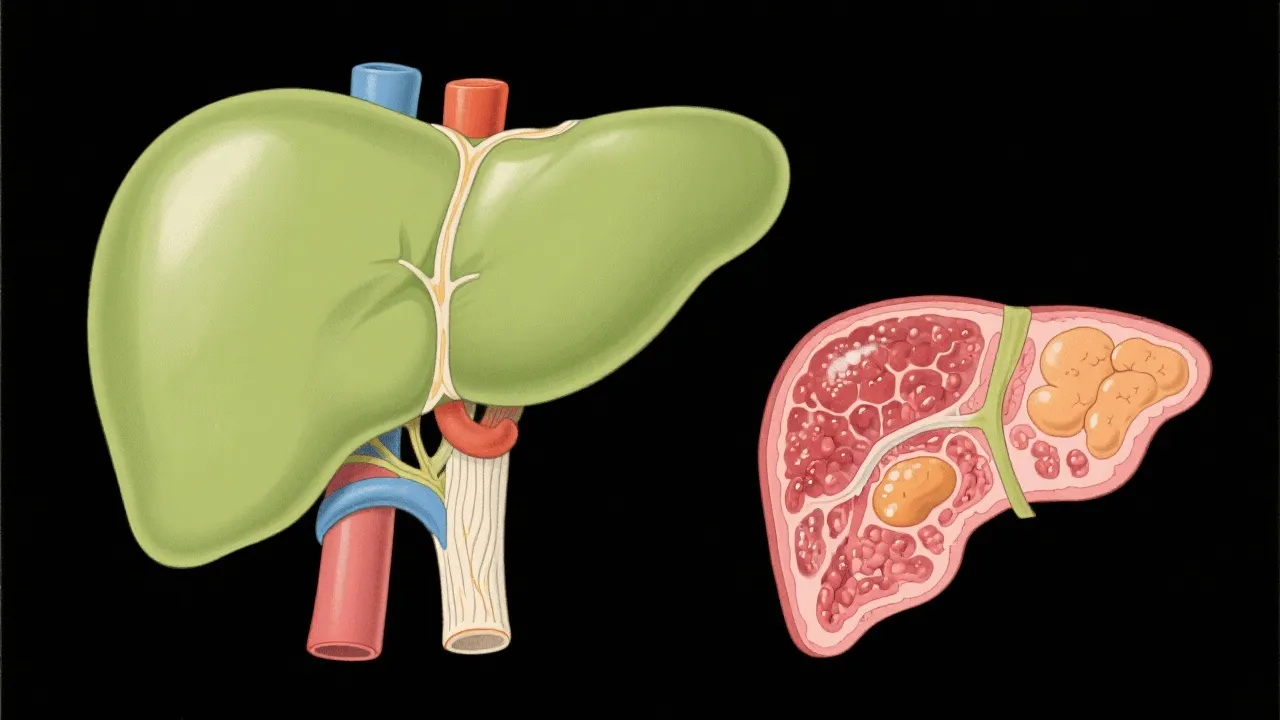

Non-Alcoholic Fatty Liver Disease (NAFLD) is increasingly becoming a major health concern across the globe due to its prevalence and potential progression to more severe liver conditions. Characterized by excessive fat accumulation in liver cells, NAFLD can progress without significant alcohol consumption, ultimately leading to inflammation, fibrosis, and cirrhosis if left unchecked. This silent disease represents a spectrum of liver conditions, with Non-Alcoholic Steatohepatitis (NASH) being a particularly severe form. The implications of NAFLD extend beyond liver health, as it is also associated with metabolic syndrome, type 2 diabetes, and cardiovascular diseases, making it a multi-faceted issue that requires urgent attention from healthcare providers and researchers alike.

NAFLD is a condition where fat builds up in the liver without significant alcohol consumption, potentially leading to liver inflammation and even cirrhosis. It has become one of the most prevalent liver diseases globally, affecting a significant proportion of adults and increasingly, children.

Long-term implications of NAFLD can include an increased risk of liver fibrosis, cirrhosis, and liver cancer. Additionally, individuals with NAFLD are at a higher risk for developing cardiovascular diseases and type 2 diabetes, highlighting the systemic nature of this condition.